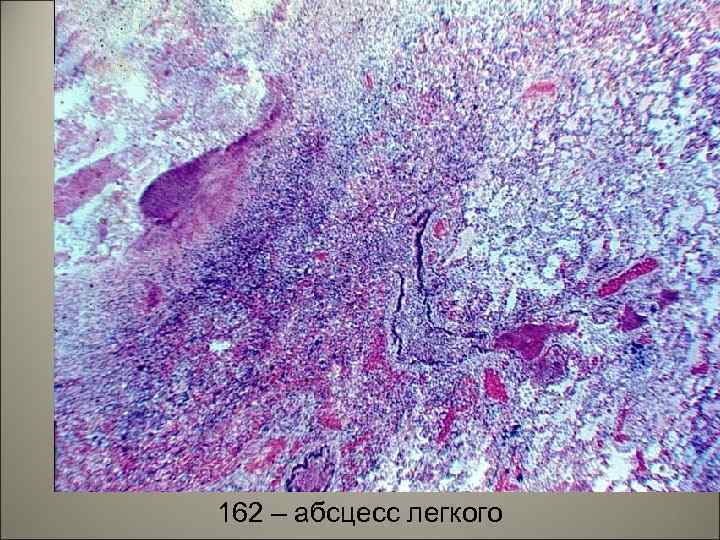

• При чрезмерной, высокой активности нейтрофилов возможно расплавление легочной паренхимы и развитие абсцессов или гангрены легкого (ткань легкого тускнеет теряет блеск). 58

162 – абсцесс легкого 59